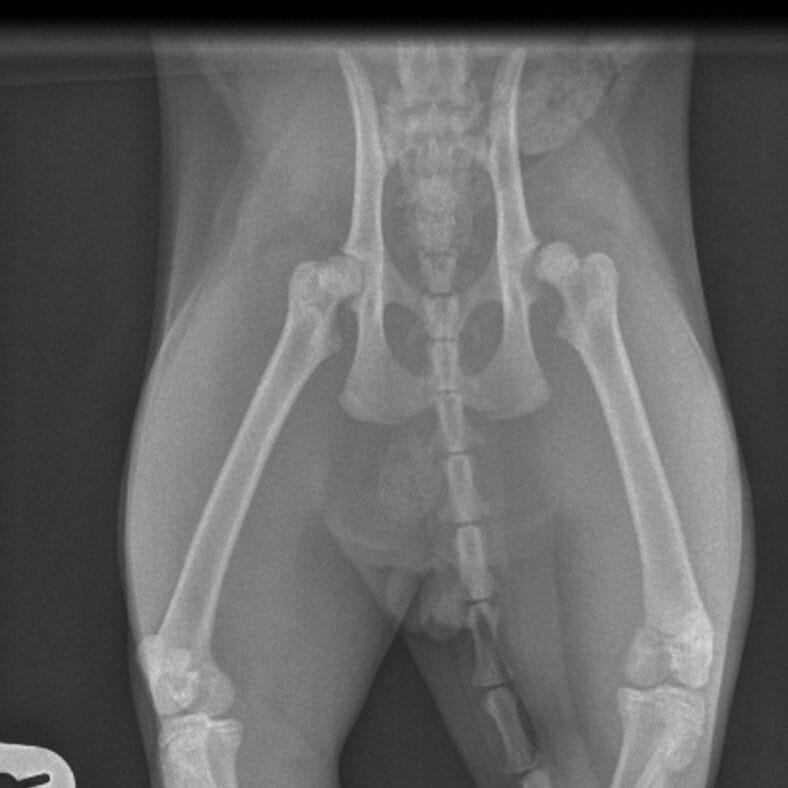

A fractured femur. A broken leg. A chest injury. A limp tail. A pelvic fracture.

After a full examination, the veterinary team found that Benito’s spine had been fractured.